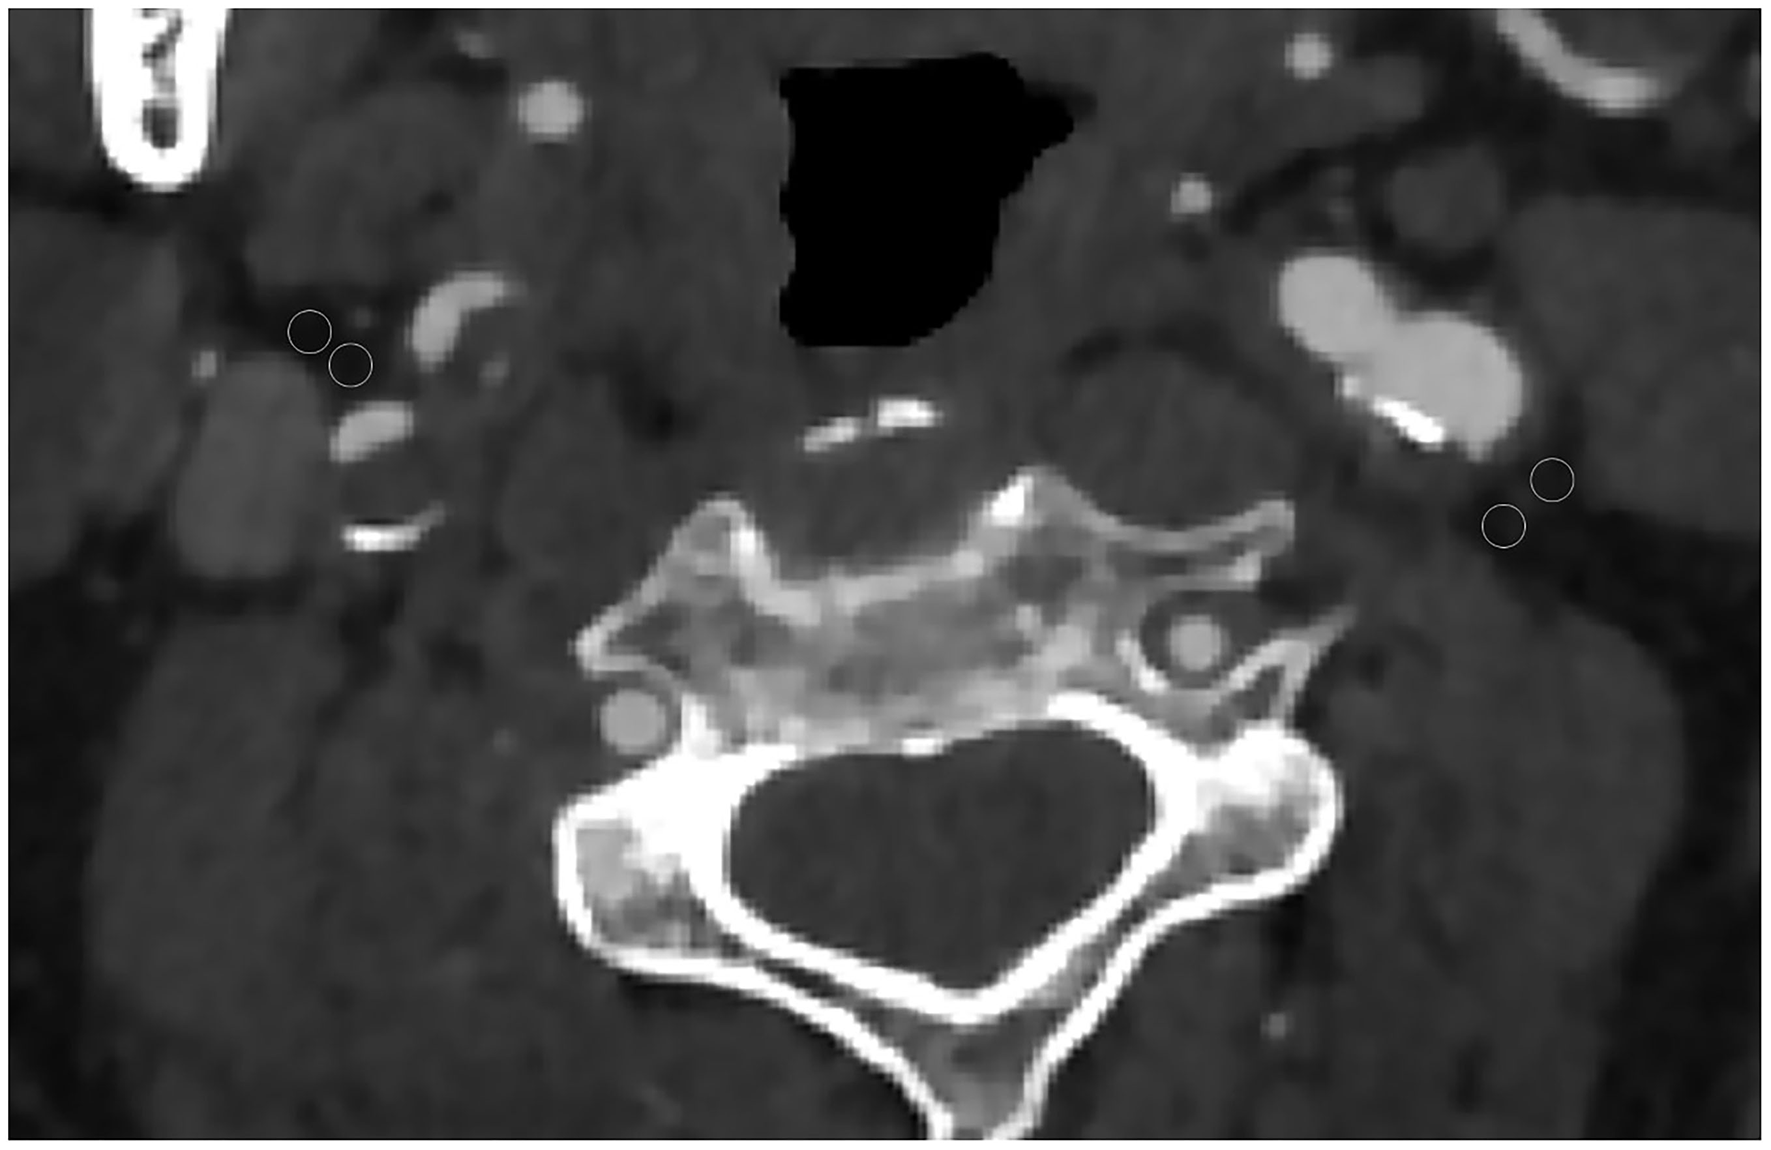

Each CTA was reviewed by two neuroradiologists who were blinded to all the clinical information including the location of cerebral infarction. The reviewer was not permitted to view additional neuroimaging other than the neck CTA. The pixels corresponding to adipose tissue were identified, and in the perivascular fat present on the same axial slice showing the maximal North American Symptomatic Carotid Endarterectomy Trial (16) defined atherosclerotic plaque or carotid artery stenosis placed 2 ROIs (each 2.5 mm2). The site of ROI placement was determined at the maximum stenosis site, location of the carotid atherosclerotic plaque, and location of the perivascular fat pads (Figure 1). ROIs were drawn carefully to only include detectable fat density (visually dark and confirmed by negative HUs). Care was taken to exclude the carotid artery wall or surrounding soft-tissue structures, with ROIs placed at least 1 mm from the outer margin of the carotid artery wall.

Figure 1

Axial CT angiography image of a 65-year-old male patient. Two regions of interest (ROIs) were placed in the perivascular fat for measured perivascular fat density. In this case, the 2 left ROIs were −60 and −68 and the 2 right ROIs were −62 and −73.